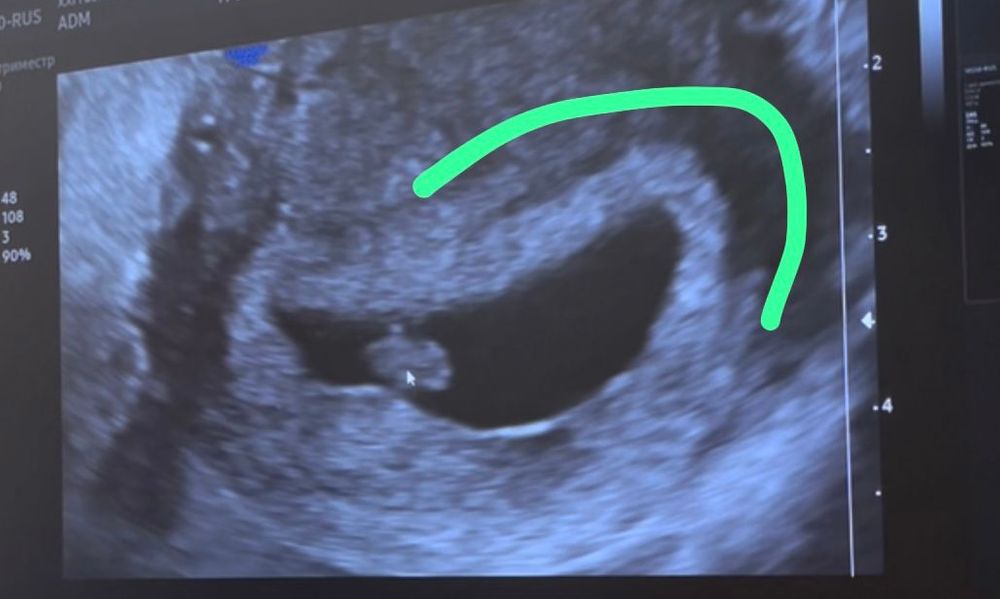

Я читала что расположение плаценты можно узнать по светлому месту вокруг амниотического пузыря. И что положение эмбриона не связано с расположением плаценты.

Эта светлая колбаска - это плацента/хорион?